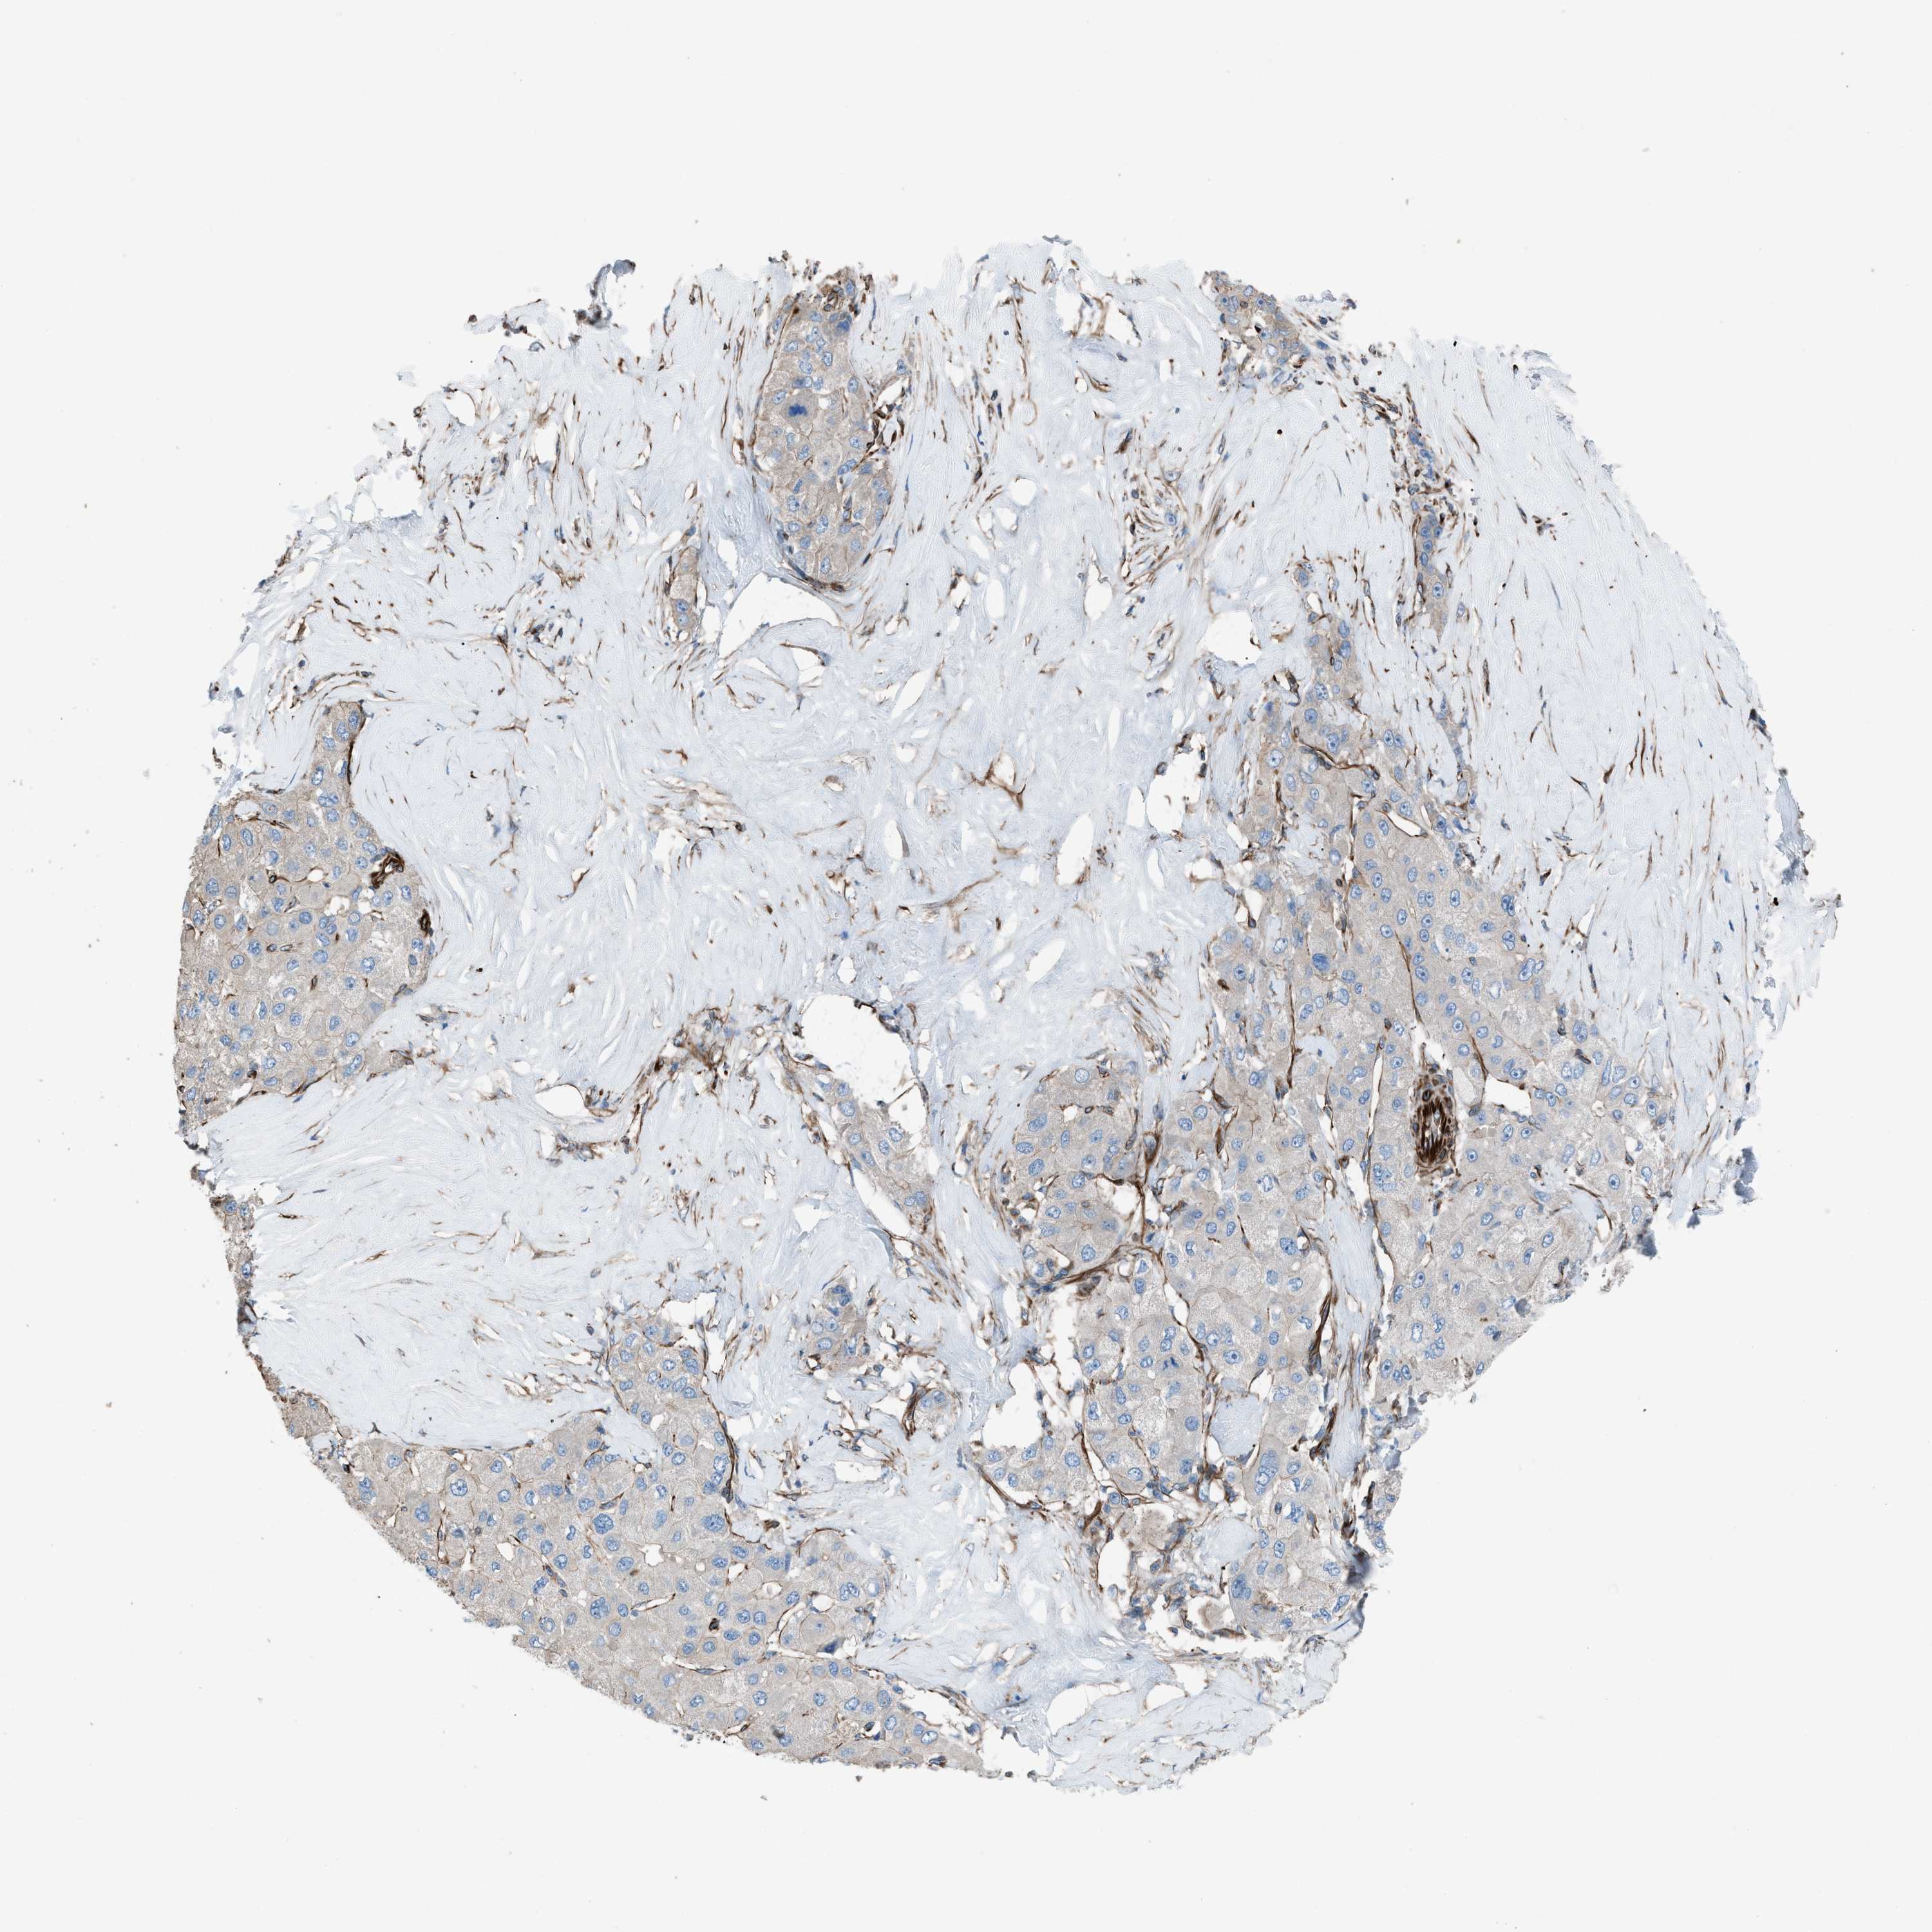

LIVER CANCER - Protein expressioni

A mouse-over function shows sample information and annotation data. Click on an image to view it in a full screen mode. Samples can be filtered based on level of antibody staining by selecting one or several of the following categories: high, medium, low and not detected. The assay and annotation is described here.

Note that samples used for immunohistochemistry by the Human Protein Atlas do not correspond to samples in the TCGA dataset.

Antibody stainingi

Antibody staining in the annotated cell types in the current human tissue is reported as not detected, low, medium, or high, based on conventional immunohistochemistry profiling in selected tissues. This score is based on the combination of the staining intensity and fraction of stained cells.

Each image is clickable and will lead to virtual microscopy that enables deeper exploration of all samples and also displays staining intensity scores, fraction scores and subcellular localization as well as patient and tissue information for each sample.

Antibody HPA016439

Staining

High

Medium

Low

Not detected

Intensity

Strong

Moderate

Weak

Negative

Quantity

>75%

75%-25%

<25%

None

Location

Nuclear

Cytoplasmic/membranous

Cytoplasmic/membranous,nuclear

Cholangiocarcinoma

Carcinoma, Hepatocellular, NOS